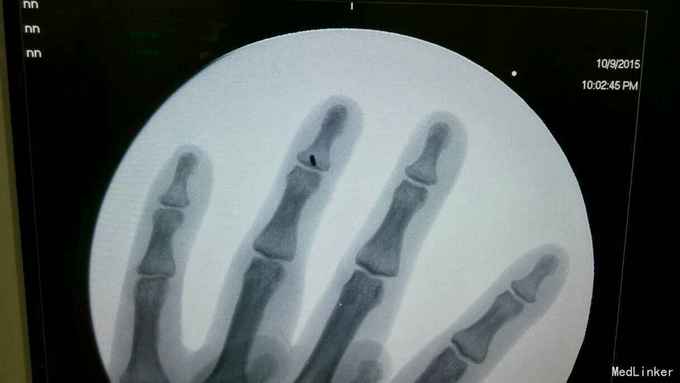

患者外伤后手指末节主动屈曲不能1周

查体可见左环指末节主动屈曲不能,被动活动正常,被动伸直时无阻力,休息位时远指间关节过伸

指深屈肌腱断裂,行指深屈肌腱止点重建,术中可见指深屈肌腱自止点处断裂,术中切开腱鞘,暴露指深屈肌腱断端,有回缩,空针头固定肌腱断端,铆钉自远节指骨基地打入,缝合肌腱断端